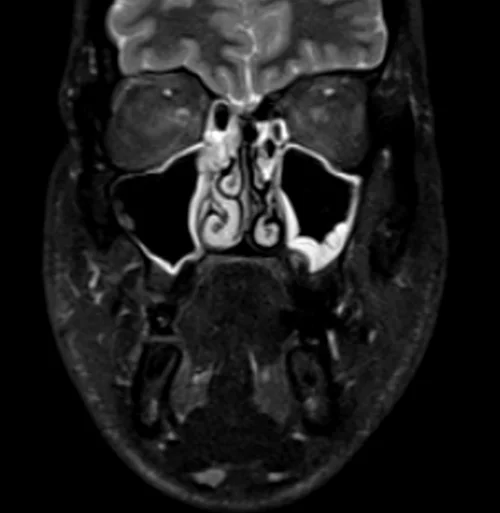

MRI face STIR coronal images